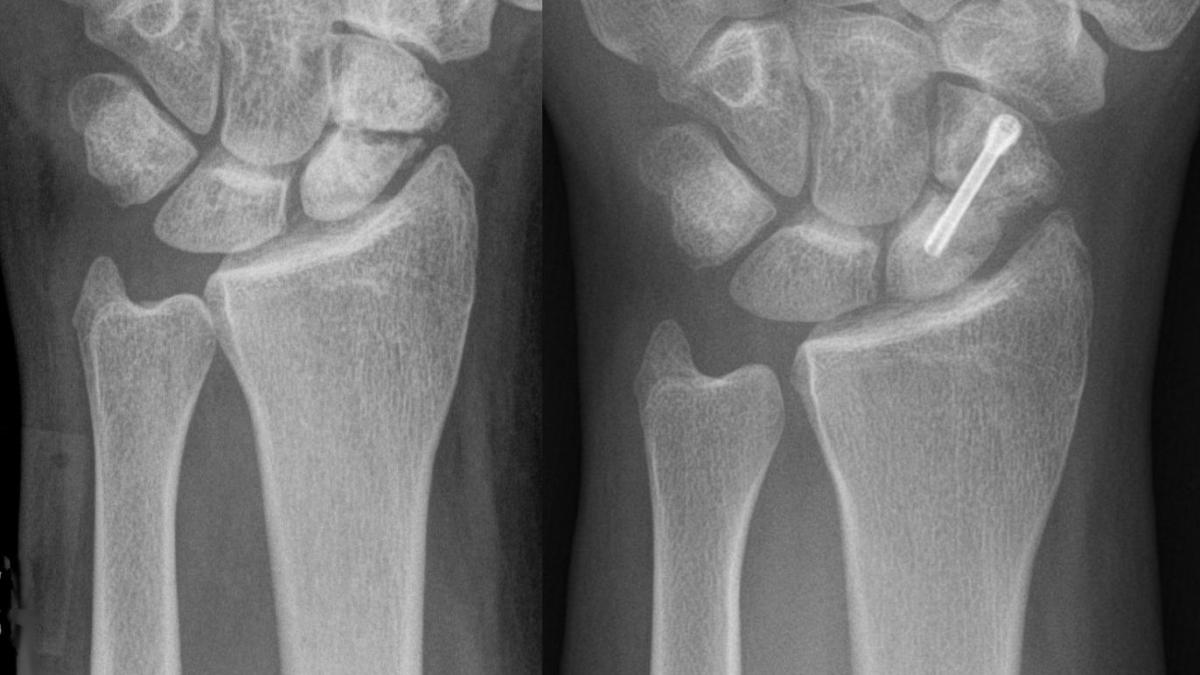

С возрастом наши кости становятся более хрупкими, что связано с уменьшением их плотности. Этот процесс особенно заметен после 50 лет, когда естественное обновление костной ткани замедляется. У женщин значительную роль в этом играет снижение уровня эстрогена после менопаузы, а у мужчин — постепенное снижение тестостерона. В результате костная ткань разрушает быстрее, чем восстанавливается, что ведет к ослаблению и потере прочности. Это увеличивает риск остеопороза, заболевания, при котором кости становятся ломкими и подверженными переломам.